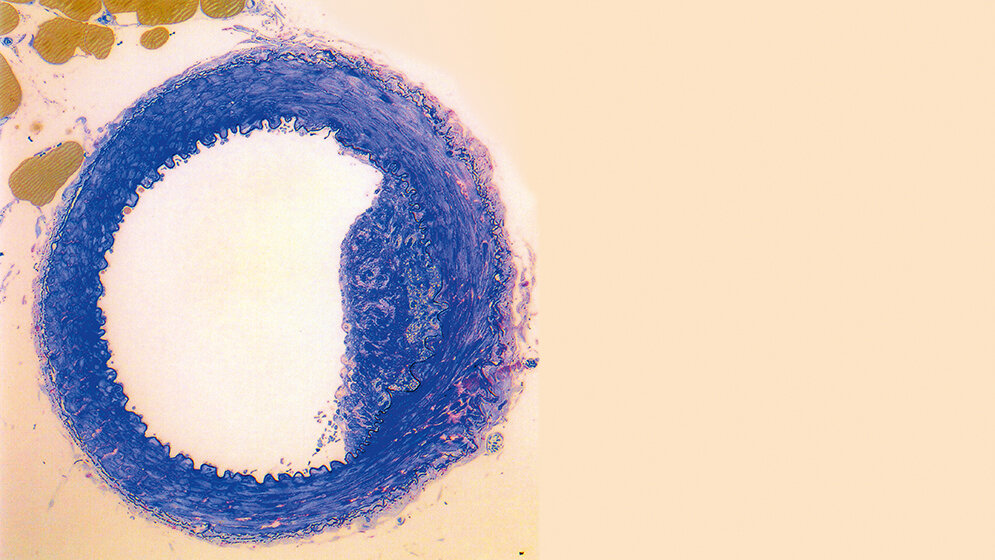

Untersuchungen der Gefäßerkrankung bei Kindern mit seltenen Störungen im Homocysteinstoffwechsel durch Kilmer S. McCully wiesen bereits Ende der 1960er-Jahre auf Homocystein als bedeutenden Risikofaktor für degenerative Erkrankungen vieler Menschen hin. McCully bekam für seine Homocysteintheorie der Arteriosklerose zeitweilig starken Gegenwind. Doch mittlerweile gehört die Bestimmung von Plasmahomocystein zu den anerkannten kardiovaskulären Risikofaktoren und wurde jüngst zudem als prädiktiver Risikofaktor für den Verlauf einer Erkrankung bei SARS-CoV-2-Patienten vorgeschlagen.

Already in the late 1960s, studies of vascular diseases in children with rare disorders in homocysteine metabolism by Kilmer S. McCully pointed to homocysteine as an important risk factor for degenerative diseases for many people. There were times, when McCully faced strong headwinds for his homocysteine theory of arteriosclerosis. However, meanwhile determining homocysteine together with other cardiovascular risk markers belongs to the clinical practice. Recently, experts suggested the routine determination of plasma homocysteine as a potential predictive marker for severe disease in SARS-CoV-2 patients.